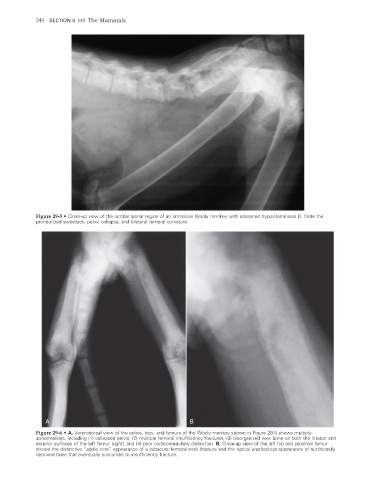

Figure 29-5 • Close-up view of the lumbar spinal region of an immature Wooly monkey with advanced hypovitaminosis D. Note the

pronounced swayback, pelvic collapse, and bilateral femoral curvature.

Figure 29-6 • A, Ventrodorsal view of the pelvis, hips, and femurs of the Wooly monkey shown in Figure 29-5 shows multiple

abnormalities, including (1) collapsed pelvis, (2) multiple femoral insufficiency fractures, (3) disorganized new bone on both the interior and

exterior surfaces of the left femur (right), and (4) poor corticomedullary distinction. B, Close-up view of the left hip and proximal femur

shows the distinctive “apple core” appearance of a subacute femoral neck fracture and the typical washed-out appearance of nutritionally

deprived bone that eventually succumbs to insuffi ciency fracture.